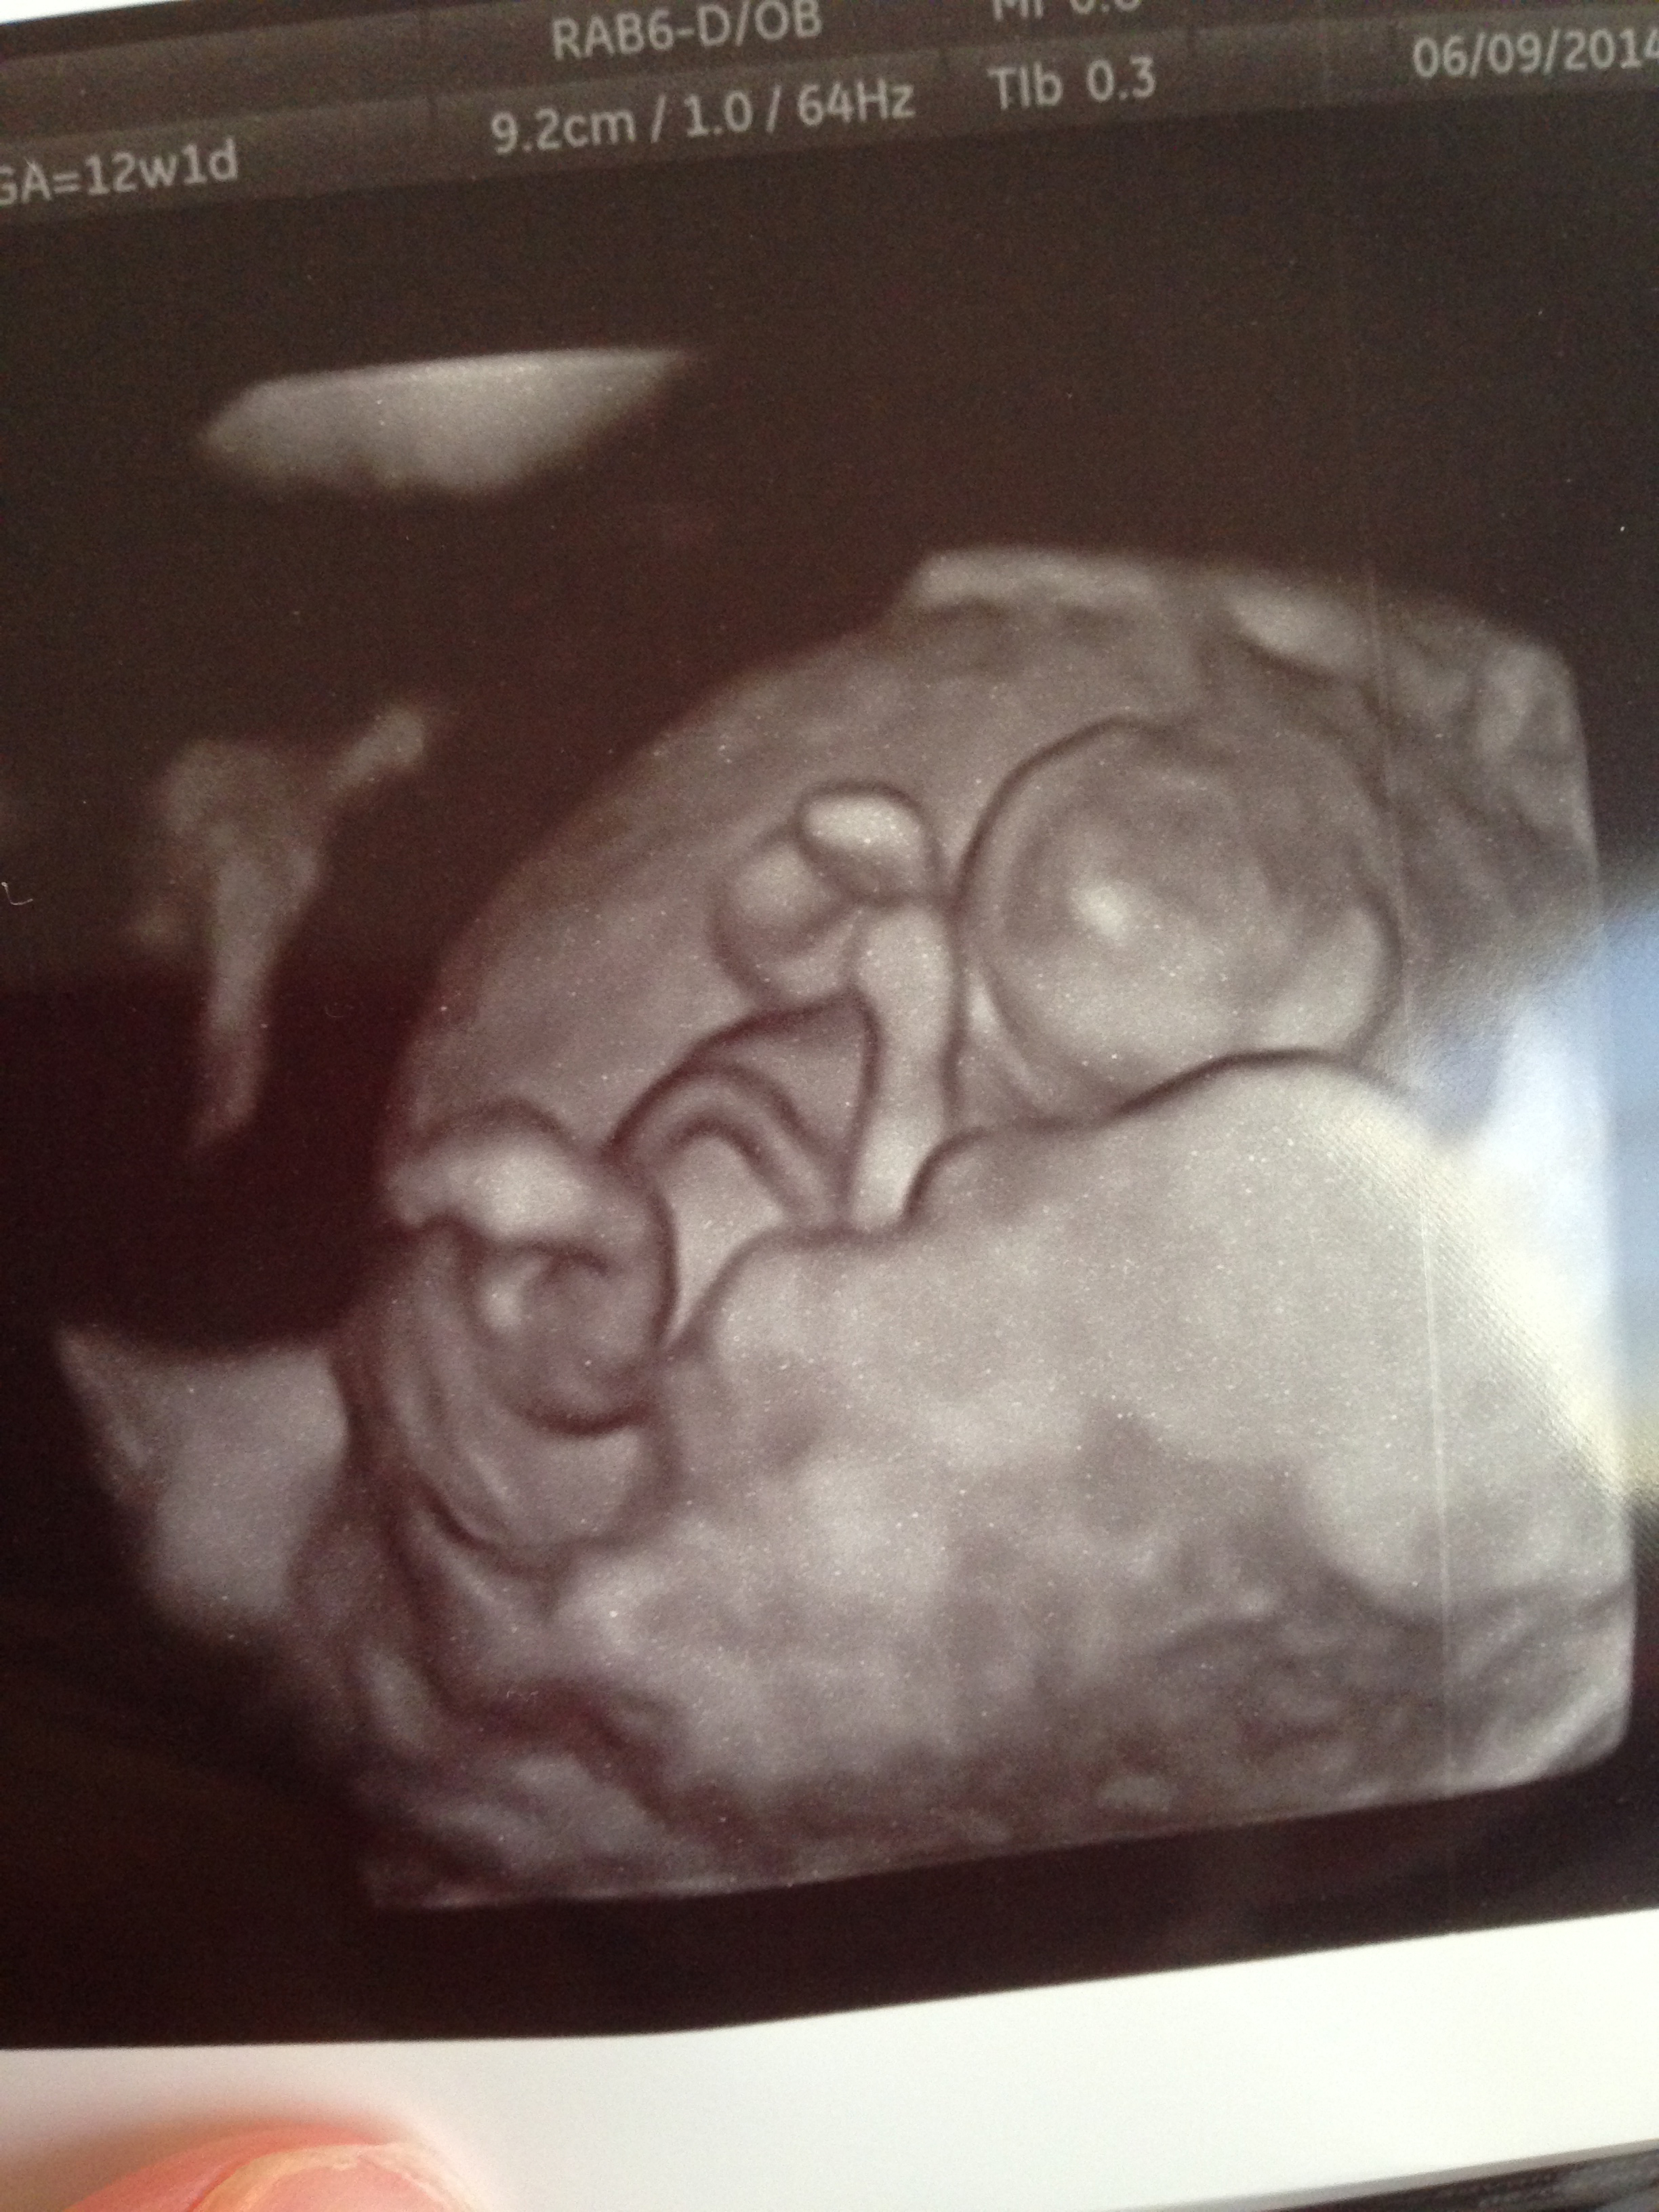

Just in case anyone wanted to compare skulls or potty shots (well upside down potty shot...lol....not the most reliable at that stage I'm sure), we got GIRL at today's ultrasound. Anyone disagree??![]()

I know it's REALLY hard to tell at this stage, and we couldn't get a good nub shot :/ Tech "didn't believe in that stuff". *shrug*. Anyway.....she did do a potty look and there was nothing there, but she said it was still too early to see anything. She did manage to print an over head shot of the legs AND a cool 3D shot that looks like there's a bulge there, BUT I know girls are really swollen at this age as well (most of the time still with a nub). So thoughts? Wanna guess? I don't even care what it is one way or the other, I'm just impatient! ha!We'll have to wait for a gender scan I guess to be sure

Here's one more if you want to a to guess based on skull